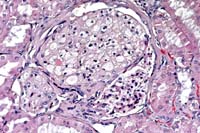

Case 14-1a. Lung. Mixed leukocytes and fibrin expand the interstitium with serofibrinous exudate and alveoli contain sloughing type II pneumocytes with diffuse basophilic nuclear inclusions. 40X

Case 14-1b. Kidney. Cortical tubule epithelium is necrotic and often contains basophilic nuclear inclusions. 40X